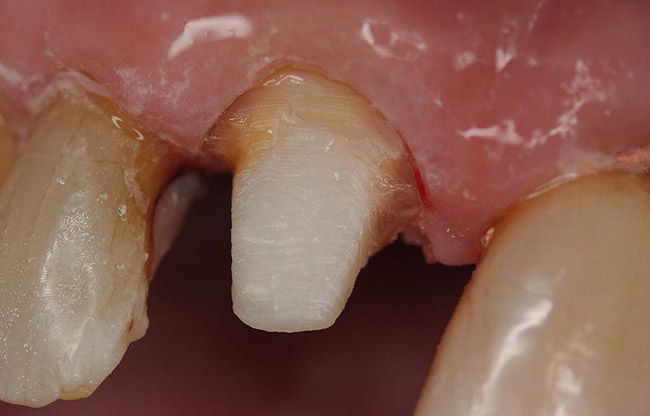

Case 1

A Class IN maxillary bicuspid was previously restored with a fiber post and an all-porcelain crown (Figure 1). The forces of the oral environment resulted in fracture of the fiber post and crown failure. The remaining fiber post in the root was removed, and anti-rotational areas were prepared for a cast post (Figure 2). A gold cast post was constructed at a dental laboratory, using an indirect technique (Figure 3). A porcelain-fused-to-metal (PFM) crown was constructed with a bevel finish to provide a ferrule and reduce forces on the post (Figure 4 and Figure 5).

Figure 2  Same second bicuspid as Figure 1 after removal of the fractured fiber post.

Figure 2